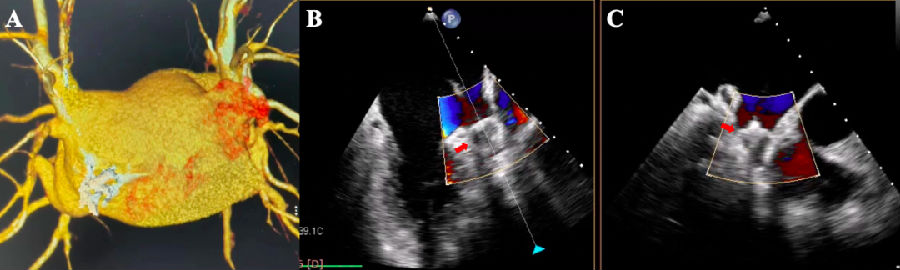

A,左心耳形态为“鸡翅型”,开口23mm;

B和C,左心耳封堵器释放后残余分流评估,泄漏量为0mm